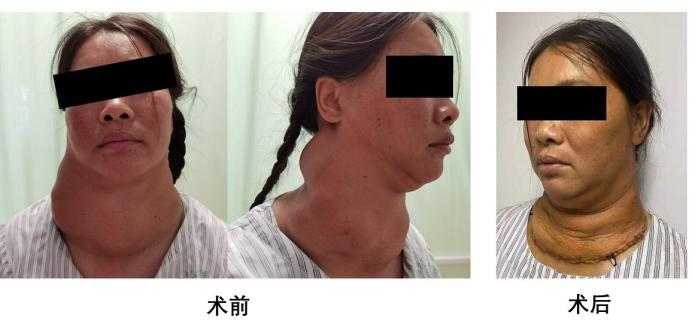

“我两年前开始觉得喘气费力,今年以来呼吸困难明显加重,严重影响日常生活。”70岁的李女士两年来因为“喘不上气”——巨大甲状腺肿瘤,曾到多地就医,均未得到有效治疗。近日,她慕名找到哈医大一院甲状腺外科代文杰教授求治。

代文杰教授团队经过充分的术前准备以及术前讨论后,由代文杰教授带领吴耀华主任医师、喻庆安副主任医师团队,在麻醉医师李淑艳麻醉下,共同为患者行经颈横切口的巨大胸骨后甲状腺肿的完整切除术。历时80分钟,将巨大甲状腺肿完整切除,避免胸骨的劈开,术后患者恢复良好,无任何神经损伤、甲状旁腺功能减退等并发症。